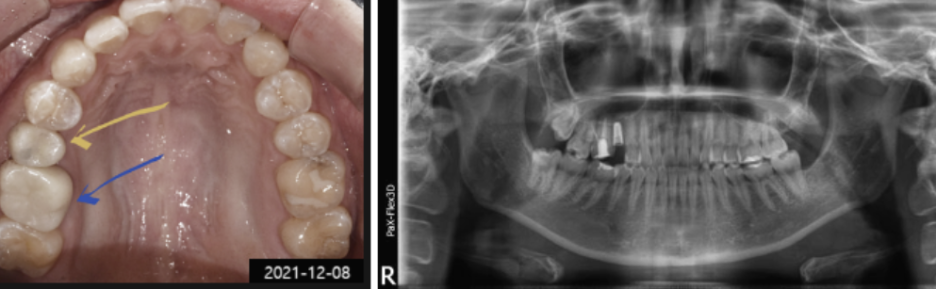

타 병원에서 치료받았던 치아에 문제가 생겨 내원하신 환자분의 사진입니다.

수일 전부터 통증이 심해서 식사도 제대로 못할 정도였는데, 보철물이 떨어져서 급하게 저희 병원을 찾아주셨습니다.

아래 사진에서 노란색 화살표를 보시면, 크라운이 탈락한 내부에 충치가 심한 것을 확인하실 수 있는데요.

내부 충치 때문에 보철물이 탈락한 것으로 보입니다.

제 경우 오래된 보철물을 교체해야 할 때 자연치아를 최대한 살리는 방향으로 진행하고 있지만,

이 환자분의 경우 자연치아를 살리기엔 이미 충치가 많이 진행되어 임플란트 교체가 불가피한 상황이었습니다.

그래서 환자분께 잘 설명해 드리고 남아있는 치아를 발치한 다음 임플란트를 진행하게 되었는데요.

사후관리의 중요성에 대해 환자분께 잘 설명해 드리긴 했지만, 재발방지 및 관리를 위해 SCRP 타입으로 진행하게 되었습니다.

SCRP 타입은 나사구멍을 통해 분리와 장착이 가능해서 사후관리 및 유지 보수에 유용하다는 장점이 있습니다.

그리고 골드 크라운이 씌워져 있던 어금니(파란색 화살표)는 내부 충치치료를 꼼꼼하게 해드린 다음,

주변 치아색과 잘 어울리는 지르코니아 크라운으로 교체해 드렸습니다.